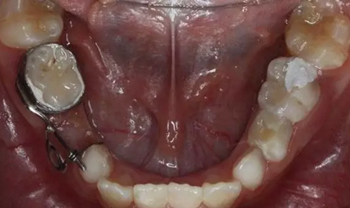

1、 患者 男 7歲 右下乳IV因齲早失

40、加力后,重新就位合面觀

42、牙面拋光,試合制作好的間隙恢復(fù)器,將曲簧水平部分形成與牙面弧形一致,羧酸鋅水門汀粘結(jié)固定

43、粘結(jié)后的頰面觀

44、8周后復(fù)診間隙推開,自動(dòng)變換為間隙保持器